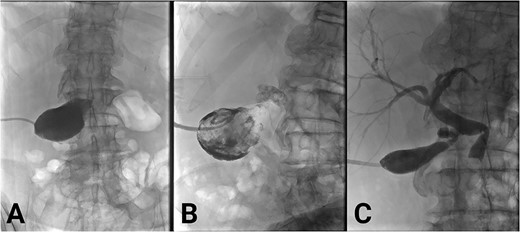

He received intravenous antibiotics, and, due to multiple comorbidities, was managed non-operatively with a percutaneous cholecystectomy. Positioning of the cholecystectomy tubing was confirmed with a cholangiogram (Fig. 2A). He developed valvular atrial fibrillation and commenced on warfarin. The sepsis resolved. He was discharged after 9 days.

(A) Initial cholecystogram showing contrast filling the gallbladder. (B) Subsequent cholecystogram showing diffuse filling defects consistent with clot in the gallbladder and cystic duct. (C) Final cholecystogram after the use of alteplase showing resolution of clots and contrast flowing into the biliary tree.

Warfarin was withheld. He was given Vitamin K and antibiotics. Over the next day, there was minimal cholecystostomy output. Pain was ongoing. On Day 2 of admission, bloods were as follows: Hb 113, WCC 20.2, INR 4.2, Bilirubin (total/direct) 61/50, ALP 730, GGT 456, ALT 412, and AST 520. A cholecystogram (Fig. 2B) Day 3 of admission confirmed ongoing biliary obstruction.

Management options were discussed with the patient, including risks and benefits of alteplase flushes. The patient consented to alteplase flushes. For 5 days, he received daily flushes, 1 mg alteplase diluted in 5 ml of saline, through the cholecystostomy tubing, which was clamped for 10 minutes afterwards.

Over 5 days, his pain resolved and liver function improved. The drain began to empty, initially blood-stained, followed by clear bile. Cholangiogram demonstrated dissolution of the intrabiliary clots (Fig. 2C). The choledocholithiasis remained. On discharge, the percutaneous cholecystectomy was draining bile freely. Warfarin was withheld indefinitely after cardiology input. After two unsuccessful endoscopic attempts to remove the choledocholithiasis with balloon ERCP, it was removed successfully by interventional radiology-guided lithotripsy. Due to comorbidities and absence of gallstones on repeat cholangiogram, the patient did not proceed to cholecystectomy. He was given ursodeoxycholic acid to prevent gallstone formation. Cholecystostomy tube was removed. He remains independent at home post lithotripsy.